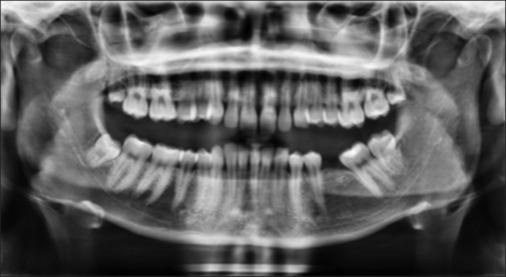

This case report details the treatment of a 23-year-old female patient with Class II division 2 malocclusion with a Class II skeletal base due to a retrognathic mandible. The condition was further complicated by a complete overbite, absence of tooth #36, and a gummy smile. The Forsus appliance has shown to be effective in correcting Class II malocclusion in adult patients, with significant improvements in bite and facial esthetics. The use of temporary anchorage devices for intrusion resulted in lower overbite and increased actual intrusion compared with alternative methods for intruding upper incisors.